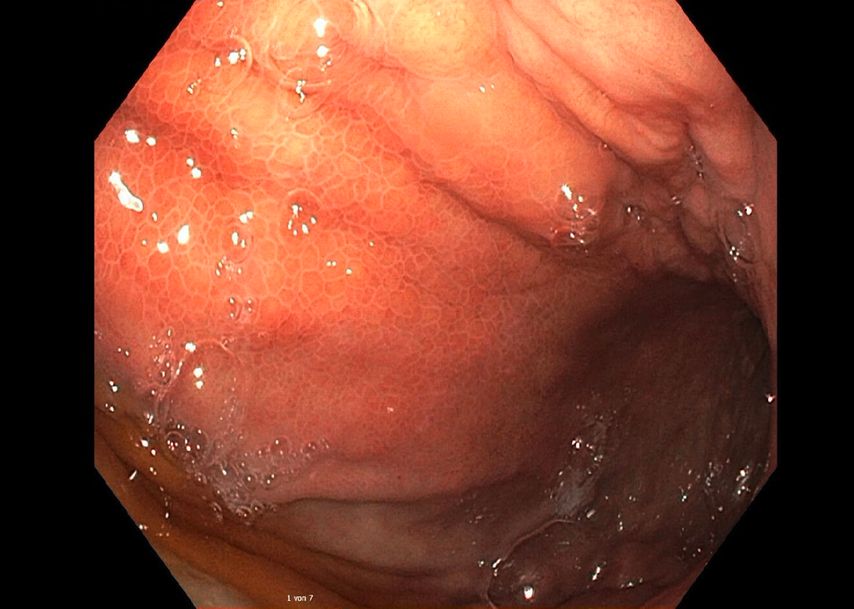

Es folgen eine sonografisch gezielte Punktion und perkutane Pigtail-Drainageanlage in die Fluidokollektion (Abb.3). Prompt entleeren sich 2,8l Pus. Die Drainage wird regelmäßig gespült und für 10 Tage belassen. In der Kultur des Punktats können Streptococcus anginosus und Klebsiella pneumoniae nachgewiesen werden, die initial eingeleitete Antibiose mit Piperacillin/Tazobactam wird antibiogrammgerecht umgestellt. Eine Kontrollgastroskopie (Abb.4) zeigt einen unauffälligen Befund am Pylorus und im Bulbus sowie in der Pars descendens duodeni, zahlreiche Biopsien der Magenschleimhaut ergeben eine geringgradige chronische, inaktive Corpusgastritis mit mukosalem Ödem.